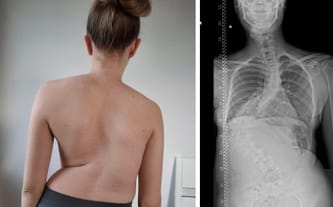

Nasze życie od kilku lat jest podporządkowane chorobie. Kiedy usłyszeliśmy o skoliozie, byliśmy przerażeni, ale wierzyliśmy, że dzięki opiece i wsparciu specjalistów, rozwój choroby uda się powstrzymać. Niestety wada postępowała, a kręgosłup Malwiny niebezpiecznie się wykręcał i krzywił. Operacja była jedynym ratunkiem.

Na szczęście przebiegła pomyślnie! Lekarzom udało się wyprostować kręgosłup ze stu stopni, do 60! Po zaledwie tygodniowym pobycie w szpitalu Malwina wróciła do domu, by cieszyć się efektami zabiegu. Stopniowo mogła podjąć czynności, które przedtem były nieosiągalne. Kilka tygodni po operacji mogła tańczyć bez obijania żeber o biodro czy pójść na siłownie i wykonywać ćwiczenia zalecone przez fizjoterapeutę.

TAK BYŁO:

TAK JEST:

Poprawa jest znaczna, jednak obecne skrzywienie nadal wywołuje dolegliwości, a pozostały garb żebrowy uniemożliwia Malwinie choćby uczestnictwo w lekcjach, Dlatego córka nadal uczy się w domu i niecierpliwie oczekuje powrotu do szkoły i rówieśników. Po konsultacjach z lekarzem włoskiej kliniki w Mediolanie zapadła decyzja o przeprowadzeniu kolejnej operacji, która jeszcze bardziej wyprostuje kręgosłup Malwiny. Termin zabiegu wyznaczono na 13. lutego 2024, a jej koszt wyceniono na ponad 65 tysięcy euro!